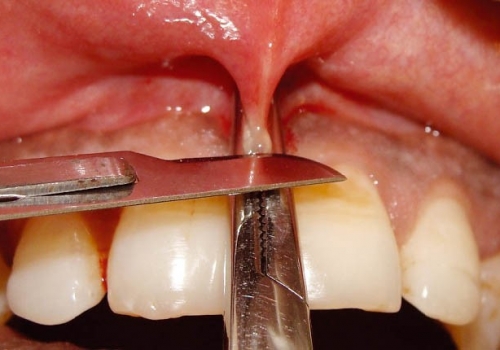

Sadalanan məhdudiyyətlərin ortadan qaldırılması və ya önünə keçilməsi məqsədilə frenulumun tamamən uzaqlaşdırılması (frenektomiya) həyata keçirilir. Bu prosedur həm ənənəvi cərrahi həm də lazer cərrahiyyəsi metodu ilə aparılır. Hansı metodun tətbiq edilməsi hər bir kliniki halda fərdi şəkildə qərara alınır.